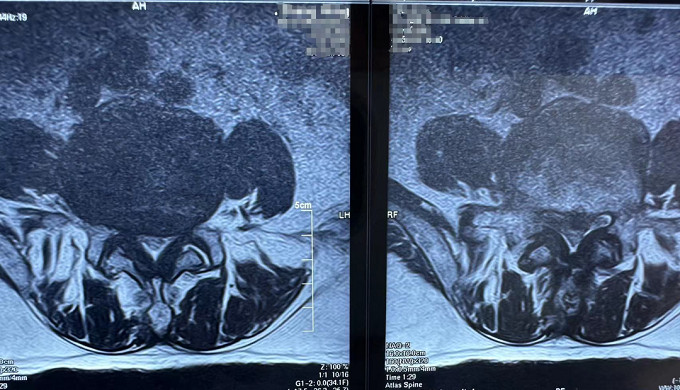

患者影像资料:

术前

核磁共振(腰椎)

可以明显的看出,患者术前椎间盘突出压迫到了神经。